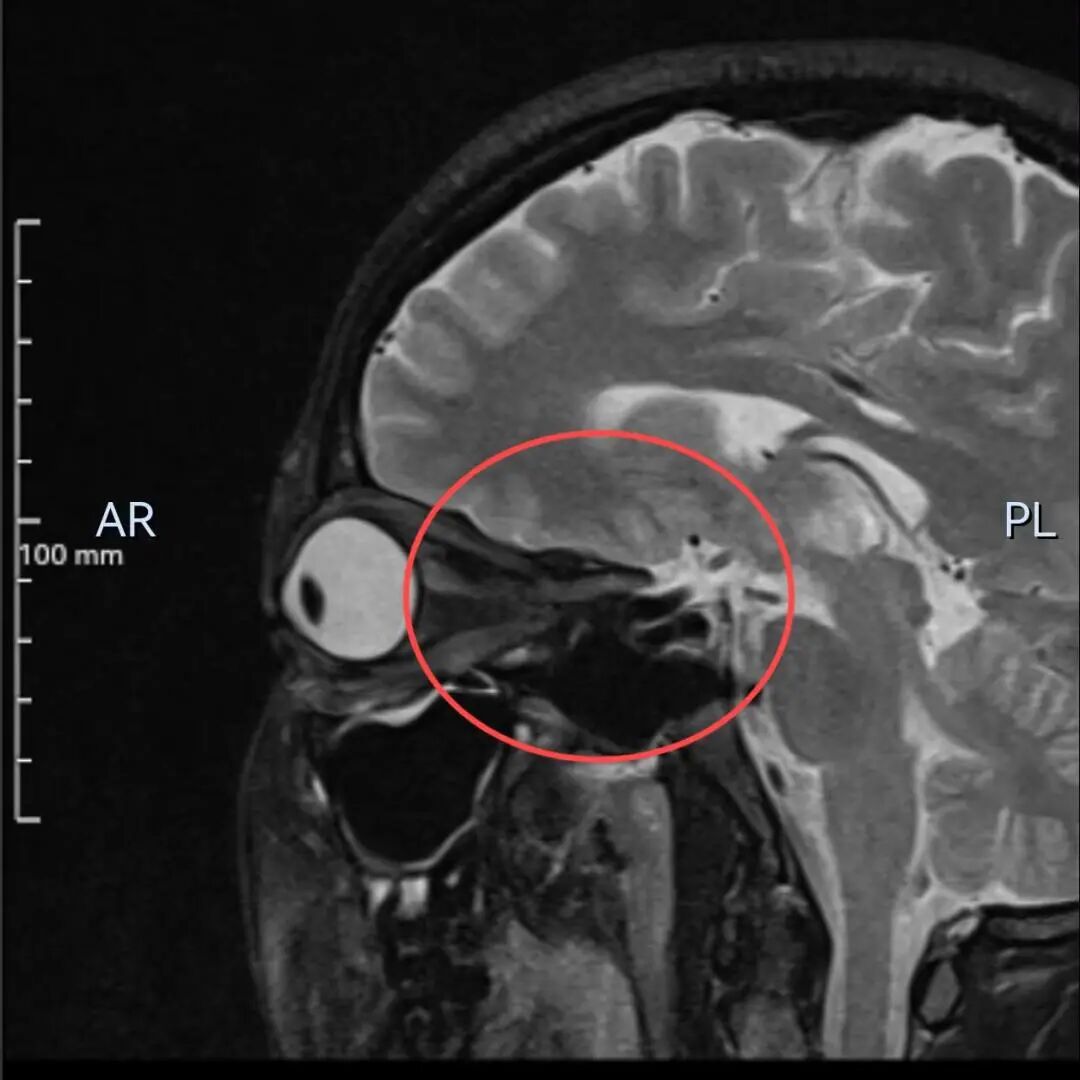

多年来,贵州航天医院各科室紧跟医学前沿,不断强技术、补短板,大力开展新技术、新项目,完成了许多高精尖、高难度、本地区“首例”的技术,填补了医院医疗技术空白,满足了群众日益增长的医疗需求。 案例分享 患者在两年前无明显诱因出现左眼胀痛、左眼视力下降等症状,由于当时患者自感不太严重,未予重视,随着时间的推移,症状逐渐加重,遂前来我院就诊,为更好的为患者进行诊治,收入了耳鼻喉科。经眼科查体显示:VOD(矫正视力)→1.0,VOS(矫正视力)→1.0,进行眼眶平扫+MRI检查后,初步诊断为:左眼球后脂肪间隙内占位,考虑良性病变,血管瘤可能。 考虑到患者病情复杂,耳鼻喉科组织眼科、麻醉科等科室开展了多学科联合会诊,对患者病情、既往病史等进行了全面深入的综合分析研讨,制定了鼻内镜下左侧鼻窦功能开放术+左侧眶内肿瘤切除术的方案,由于手术难度较大,在充分告知手术风险及并发症等相关信息后,患者及家属同意手术。经过充分的术前准备,耳鼻喉科借助经鼻内镜,成功通过鼻窦经由筛窦眶纸板、蝶窦外侧壁将肿瘤完整切除,最大程度地保护了眶内的血管、神经等重要组织。 术后,患者未出现视力减退、视野缺损等并发症,仅眶周稍青紫肿胀和轻微复视。患者2周后复查,复视症状、眶周青紫肿胀消除,术后MRI(眼眶平扫+增强扫描)显示左眶内肿物已消失。 该技术的开展,特别邀请了中山大学附属第一医院耳鼻喉科专家左可军教授莅临主刀,并对该技术的实施进行指导,已成功完成多例鼻眼相关内镜手术,解决了患者外出就医难、排队时间长、花费多等难题,让广大民众在家门口享受到了优质的医疗服务资源。 什么是鼻内镜下经鼻腔、 鼻窦进路眶内肿物切除术 眼眶是一个狭小的解剖间隙,结构复杂,功能重要,周围临近组织较多,含有许多重要结构,眶深部的肿瘤切除手术难度大,容易侵犯神经,出现视力丧失等并发症。随着眼-鼻相关学科发展和微创理念的深入,鼻内镜内侧开眶入路得到显著发展和应用,鼻内镜下经鼻腔、鼻窦进路眶内肿物切除术,具有微创、直视、并发症少等优势,目前已成为眶内肿物切除首选手术进路,主要应用于泪道系统疾病、眶骨折修复、眼眶内侧肿瘤切除、眼眶减压、海绵状血管瘤切除等。 鼻内镜下经鼻腔、鼻窦 进路眶内肿物切除术原理 手术基于先进的鼻内镜设备,通过鼻腔入路直接对眼眶及其毗邻区域进行操作,鼻腔与眼眶相邻,眼眶内侧壁主要由筛骨纸板构成,骨质菲薄,很容易经此进入眼眶,所以鼻腔可作为合适的手术通道,让操作更精准、更微创,同时,内镜下经鼻眼眶手术可利用该通道实现面部无切口。 鼻内镜下经鼻腔、鼻窦 进路眶内肿物切除术优势 ✔肿物可完整切除,较好的保护视力。 ✔可避免眼外部入路及经颅开眶入路的头面部切口。 ✔无脑组织的牵拉损伤,对眼内容物的牵拉损伤较小。 ✔经鼻切口外形无改变,术中组织结构放大、视野清晰,肿物分离更便捷。 贵州航天医院耳鼻喉科专家团队 左可军 中山大学 附属第一医院耳鼻咽喉科 贵州航天医院耳鼻喉科 特聘教授 医学博士 硕导 主任医师 临床擅长:鼻科、鼻眼相关外科、鼻颅底相关外科以及鼻变态反应科的临床和基础工作。 南方青年鼻科联盟创始人,担任中国医师协会耳鼻咽喉科分会整形美容学组委员、海峡两岸医药卫生交流协会眼科学专业委员会眼科内窥镜微创手术学组委员、广东省精准医学应用学会头颈肿瘤分会副主委、广东省中西医结合学会耳鼻咽喉科分会副主委、广东省眼健康协会眼与全身疾病专业委员会常委。获得国家二级运动员和南粤优秀研究生称号,2018年荣获“广东医院最强科室之实力中青年医生”,2020年荣获全国卫生健康系统抗疫先进集体、中国医师协会耳鼻咽喉头颈外科分会抗疫先进个人,2021年荣获广东省科技进步一等奖,2023年荣获第七届“羊城好医师”。 张光进 耳鼻喉科主任 副主任医师 临床擅长:对耳鼻喉头颈常见病的诊治具有丰富的临床经验,擅长鼻内镜、耳内镜、耳显微、头颈咽喉部肿瘤及眩晕手法复位等的诊疗。 曾先后前往第三军医大学西南医院、复旦大学耳鼻喉科医院、上海新华医院及北京友谊医院进修学习;遵义市医学会常务委员;主持及参与级科研课题2项,发表专业论文10余篇。 陈维信 耳鼻喉科 主任医师 临床擅长:对耳鼻喉科常见疾病的诊治具有丰富的临床经验,擅长耳、鼻、喉及头颈部位的手术。 曾先后前往上海交通大学附属仁济医院耳鼻喉-头颈外科、北京大学人民医院耳鼻喉-头颈外科参加鼻内镜外科进修学习。中国睡眠研究会委员,贵州省医学会耳鼻喉-头颈外科学分会委员,贵州省耳鼻喉-头颈外科学会理事,贵州省医学会变态反应学分会委员,贵州省防聋治聋技术指导组专家,遵义市耳鼻喉科分会副主任委员,遵义市医疗事故鉴定专家库成员;主持省部级科研课题2项,发表专业论文20余篇。 秦 晋 耳鼻喉科 副主任医师 临床擅长:对耳鼻喉科常见疾病的诊治具有丰富的临床经验,擅长耳、鼻、喉及头颈部位的手术。 遵义市医学会常务委员;曾先后在第三军医大学西南医院、湖南湘雅鼻颅底培训班进修学习。 贵州航天医院耳鼻喉科简介 基本情况 贵州航天医院耳鼻喉科拥有一支经验丰富、技术精湛的医疗团队,共有医师9名,其中副高级以上专家5名,医学硕士2名,开放床位20张,拥有德国WOLF鼻窦内窥镜系统、日本奥林巴斯电子喉镜、奥林巴斯电子鼻咽镜、丹麦临床听力监测设备、声导抗仪、听觉诱发电位、耳声发射仪、美国杰西低温等离子治疗仪、杭州好克鼻窦内窥镜系统、鼻动力系统、耳显微镜、耳用电钻、微波治疗仪等先进设备。 专科特色 (一)耳部疾病 耳内镜下胆脂瘤切除术、III型鼓室成形术+人工听骨听骨链重建术。 (二)鼻部疾病 内镜下鼻息肉切除术、鼻窦功能开放术。 (三)咽喉疾病 内镜下扁桃体、腺样体低温等离子切除术。 (四)交叉学科 1.经鼻内镜下眶内肿瘤切除术 2.经鼻内镜下鼻腔泪囊吻合术 诊疗范围 (一)常见耳疾的诊断和治疗:中耳炎、耳聋、耳鸣等。通过各种耳科检查手段,如耳镜检查、听力测试和耳脑干听觉诱发电位检查等,准确诊断患者病情,制定个性化治疗方案。 (二)鼻炎、鼻窦炎、鼻出血等鼻科疾病的诊断和治疗:采用微创技术,如鼻内窥镜检查、低温等离子手术等,为患者提供有效的治疗方案。 (三)喉炎、声带息肉、声带白斑等喉科疾病的诊断和治疗:通过声带电子镜、喉镜等设备,准确判断患者的喉部病变,为患者提供精准的治疗方案。 (四)鼻眼、鼻颅底相关手术。